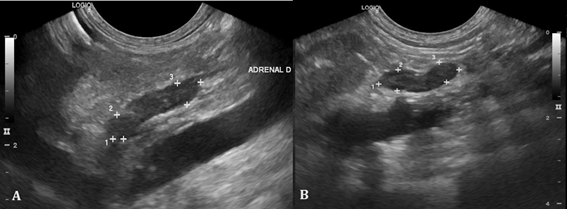

Abdominal ultrasound revealed a decrease in the size of adrenal glands (Figure 2) and hepatosplenomegaly compatible with hepatic steatosis (Figure 3).

Figure 2 Ultrasound of adrenal glands. A. Right adrenal gland measuring 1.44 x 0.46 x 0.43cm (length x height of cranial pole x height of caudal pole). B. Left adrenal gland measuring 1.12 x 0.36 x 0.33cm (length x height of cranial pole x height of caudal pole).